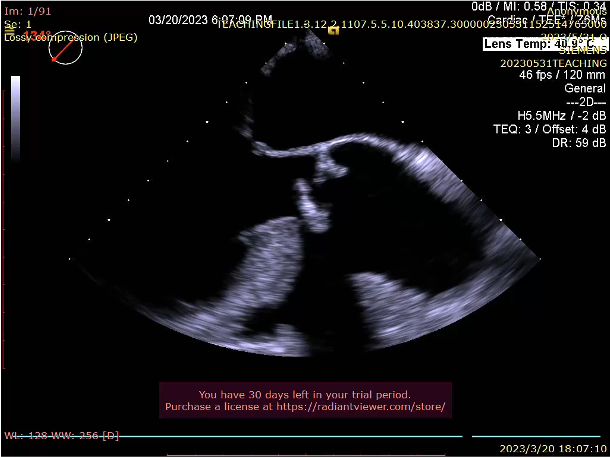

2D echo suggestive of severe aortic regurgitation. CT analysis done and we decided to opt for 24mm TAVR valve

SEV 24mm. was deployed and during reheathing patient developed circulatory collapse.

SEV 24 mm was chosen based on CT measurement and bifemoral access was obtained. Carotid filter was placed for cerebral protection.During resheathing of the valve there was sudden circulatory collapse. CPR started and left coronary catheterisation revealed occlusion of left main. Flow was established in LAD with immediate wiring and ballooning. Finally TAVR valve was deployed after LAD flow was established.LCX flow was then resolved and LM bifurcation PCI was done using crush technique Patient was finally discharged in hemodynamically stable condition.